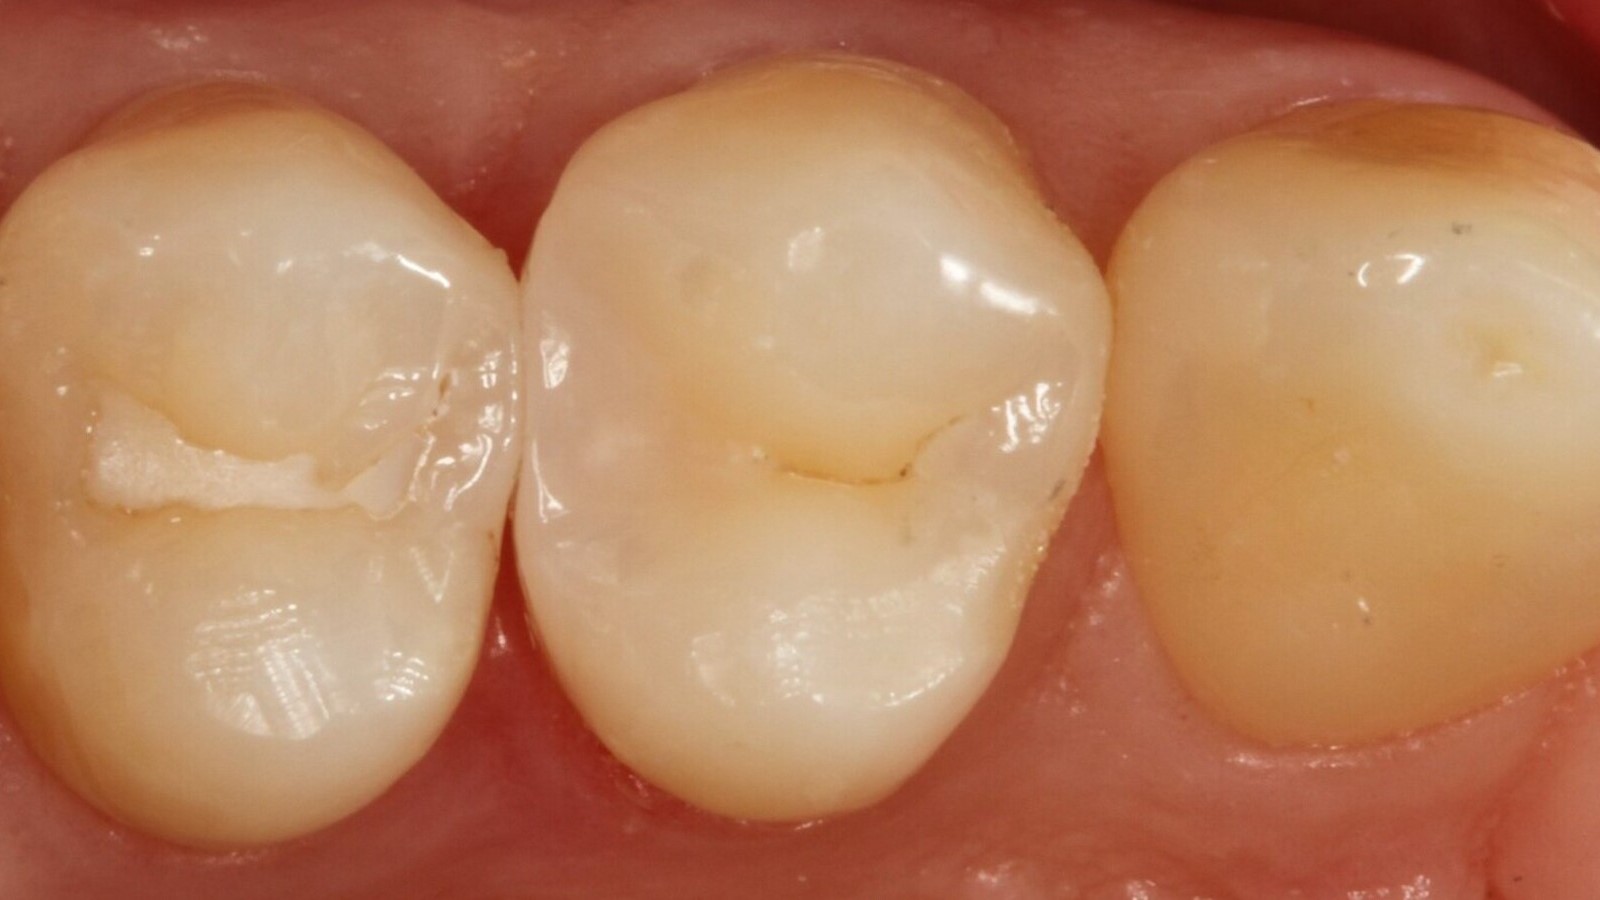

Professor Ernst identifizierte zunächst die versteckte Karies und öffnete die kariöse Läsion, um dem Patienten das Problem zu veranschaulichen (Abb. 1-2). Anschließend exkavierte er die Karies, präparierte die Kavität und setzte eine Teilmatrize ein (Abb. 3), bevor er die Kavität mit Adhäsiv versiegelte (Abb. 4). In einem einzigen Schritt füllte er die Kavität mit Venus Bulk Flow ONE (Abb. 5). Nach der Fertigstellung polierte Prof. Ernst die Restauration (Abb. 6) und fertigte ein Kontrollröntgenbild an, das ebenfalls die hervorragende Röntgenopazität von Venus Bulk Flow ONE zeigt (Abb. 7).